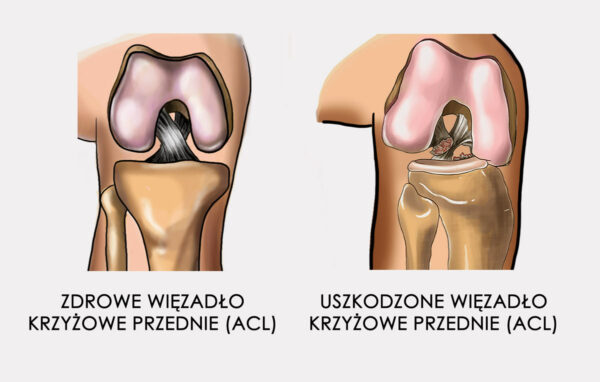

USZKODZENIE WIĘZADŁA KRZYŻOWEGO TYLNEGO (PCL)

Więzadło krzyżowe tylne (PCL) to solidne pasmo tkankowe, łączące kość udową z piszczelą, które jest znacznie mocniejsze niż ACL. Wraz z więzadłem krzyżowym przednim (ACL) zabezpieczają dolną część kości udowej i górną część kości piszczelowej, co pozwala na utrzymanie tych dwóch kości wspólnie i formowanie stawu kolanowego. Więzadła krzyżowe stawu kolanowego pozwalają nam żyć aktywnie: skakać, pływać czy biegać. Problem polega na tym, że podczas tych aktywności więzadła krzyżowe oraz okoliczne tkanki miękkie mogą zostać łatwo uszkodzone. Wraz z uszkodzeniem PCL bardzo często dochodzi do zerwania innych więzadeł kolana, a także do uszkodzenia chrząstki stawowej czy łąkotki.

Więzadła krzyżowe stawu kolanowego pozwalają nam żyć aktywnie: skakać, pływać czy biegać. Problem polega na tym, że podczas tych aktywności więzadła krzyżowe oraz okoliczne tkanki miękkie mogą zostać łatwo uszkodzone. Wraz z uszkodzeniem PCL bardzo często dochodzi do zerwania innych więzadeł kolana, a także do uszkodzenia chrząstki stawowej czy łąkotki.